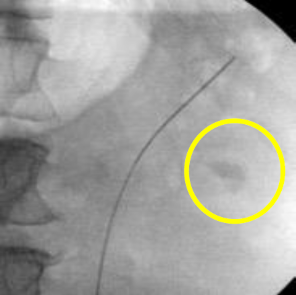

A decision was made to proceed with ureteroscopy. A pre-operative urine culture was obtained to rule out infection. Scout fluoroscopic images demonstrated the stone in an interpolar calyx (Figure 10). A flexible ureteroscope was used in this case without an access sheath. The scope was advanced over the wire into the kidney.